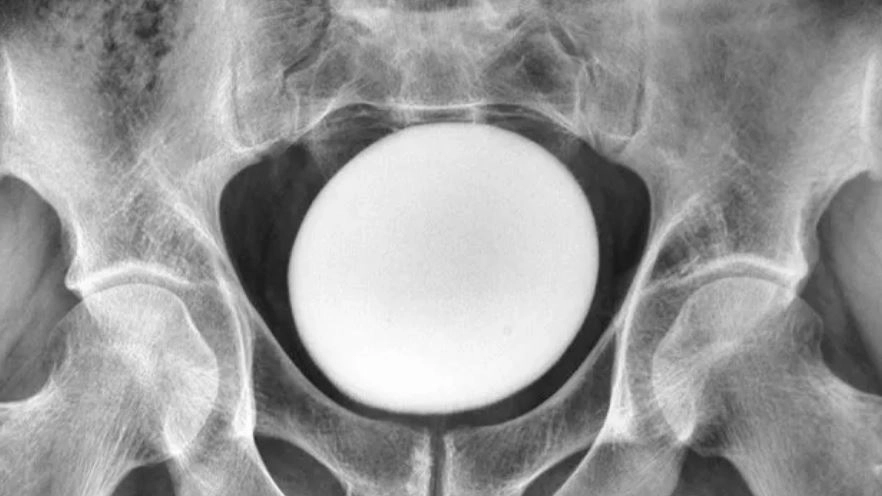

이 덩어리는 골반이나 복벽에 붙어있지 않았다. 초음파 검사 결과 지름 약 11㎝의 달걀 모양 물체였다.

의료진은 이를 비정상적으로 큰 방광 결석으로 진단했다. 결석은 소변 속 미네랄이 결정으로 쌓이면서 자라는데, 약 85%가 칼슘으로 이뤄져 있다.

꺼낸 결석은 무게 826g, 길이 약 13㎝, 너비 약 10㎝, 높이 약 8㎝였다.